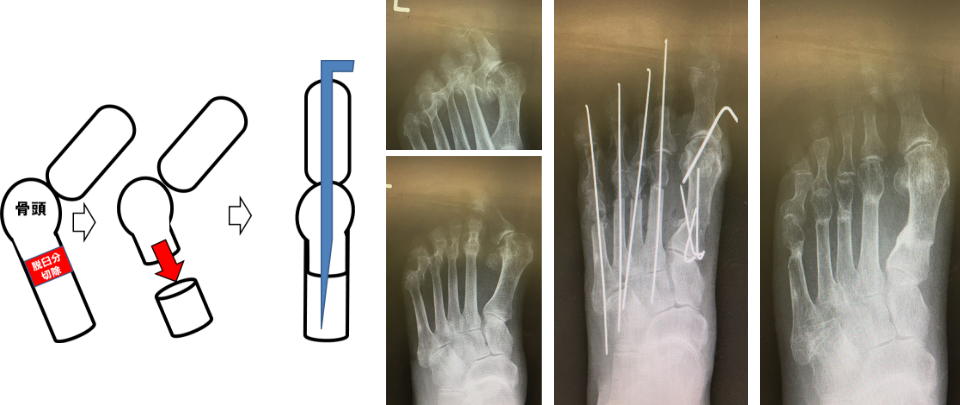

RAの前足部変形に対する関節温存手術

RAの前足部障害は多く認められ、末期には中足骨頭が底側に脱臼し、足底に胼胝を形成します。治療は脱臼した中足骨頭を切除する切除関節形成術が行われていましたが、近年薬物による関節修復の可能性や関節機能を再獲得する目的で関節を温存する手技に変わりました。手技は左図のように中足骨骨幹部遠位を短縮骨切り後、中足骨頭を近位へ引っ張り脱臼を整復して関節を温存します(図12)。これにより可動域や踏み返しが可能となり除痛、さらに地面をとらえた良好な歩容を目指します。

図12 RAに対する関節温存手術